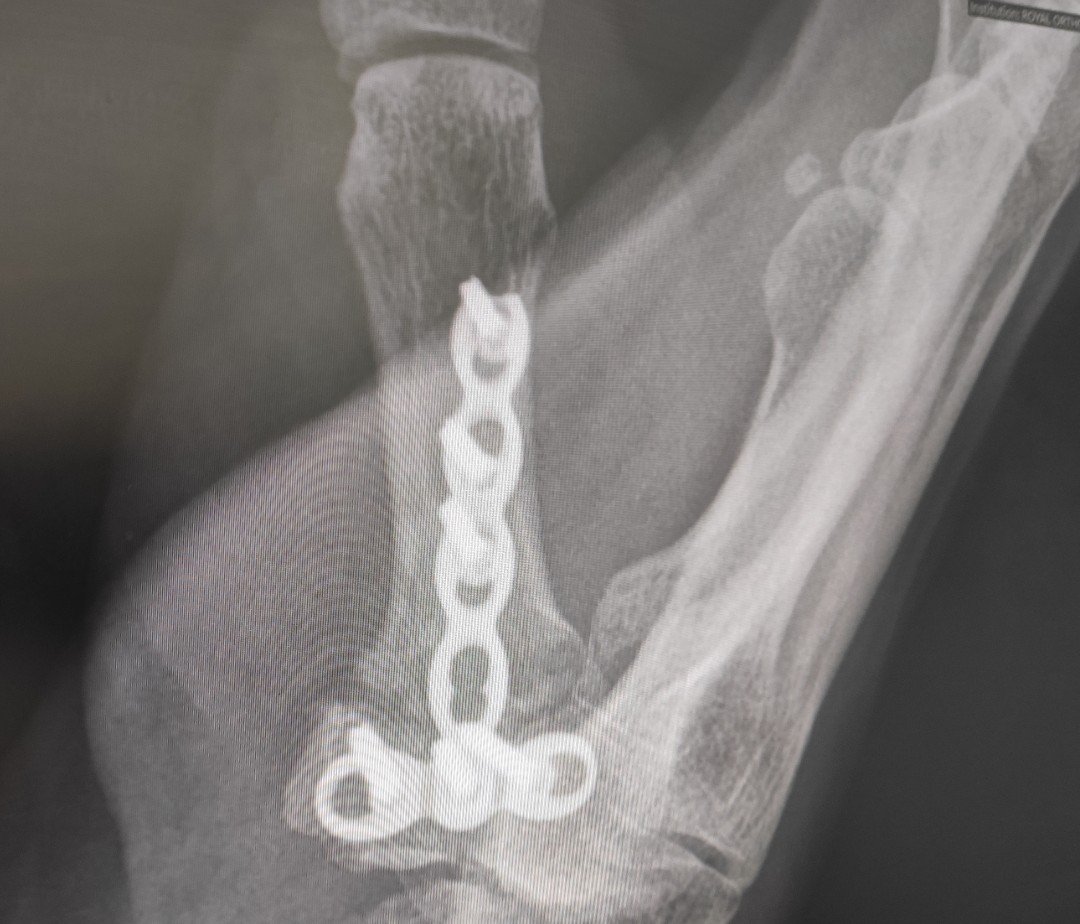

ZERO change in x-ray, so the plan is more splint wearing for 4 to 5 weeks, with some thumb exercises, I had been doing anyways but more stretching. Splint wasn’t updated but I did get a repair kit, extra straps, pink edging, and velcro to replace as needed. Felt nice to know I’m doing what is needed already, and they are happy with that progress.

I can just about touch the third finger for the briefest second, so the plan and aim is to do more, maybe get to pinky finger (🤪) and slide thumb tip down the fingers. Asked about the other hand, and as her waiting list is small if she put me on it, I’d be called up within a month. So better to leave it until left hand is splint free and strong. She did say she might remove the plate, have more x-rays and a CT scan before she makes a decision. I’m allowed to take my Etoricoxib tablets but I’m hesitant as it will hinder bone growth, so maybe waiting another 5 weeks won’t hurt, I’ve done 7 weeks already.